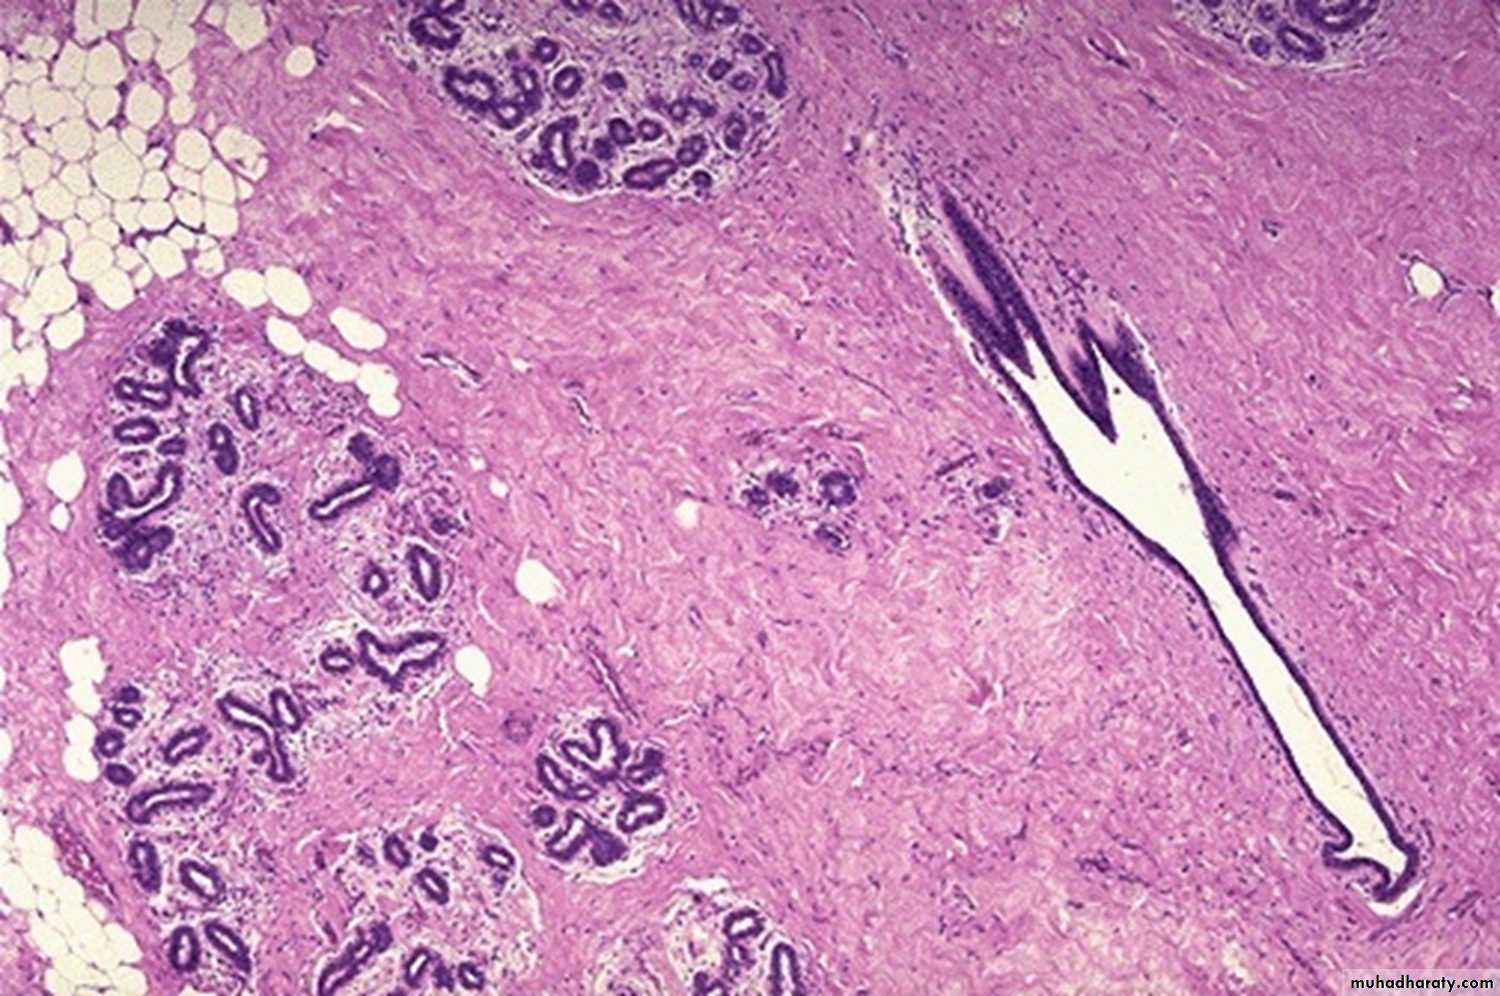

Fibrocystic disease: fibrosis, formation of cysts which are lined by flattened cuboidal epithelium, and adenosis.

Intracanalicular fibroadenoma: stromal proliferation compresses the ducts which are irregular and reduced to slits.Duct papilloma: branching fibro vascular stromal core covered by cuboidal epithelium